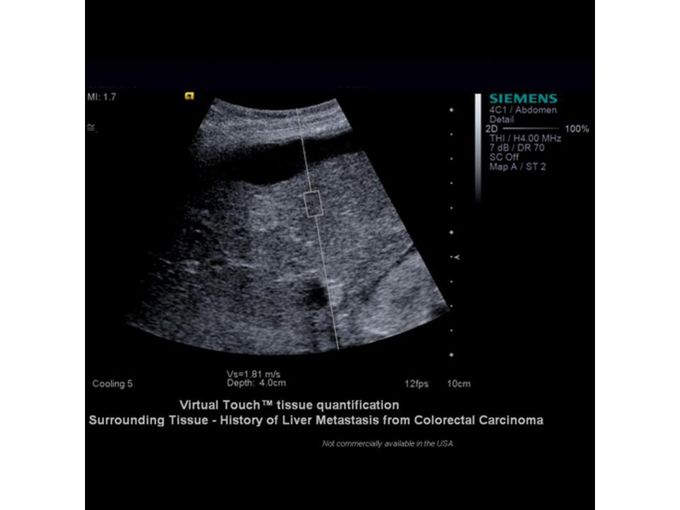

Кроме новой техники, можно заказать восстановленные медицинские системы: ультразвуковые сканеры, томографы, флюороскопы, ангиографы и хирургические установки С-дуга.